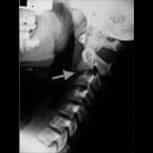

A nossa orientação médica é gratuita para casos de DOENÇA DO FILUM e de patologias que fazem parte dela: a Síndrome de Arnold-Chiari I, a Escoliose idiopática, a Siringomielia idiopática, a Platibasia, a Invaginação Basilar, a Retroflexão do Odontóide e a Angulação do Tronco Cerebral.

Síndrome de Arnold Chiari I,

Escoliose e Siringomielia idiopáticas.